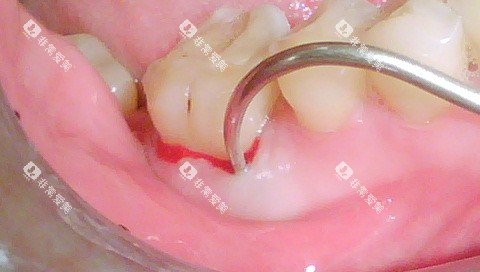

根管治疗主要用于治疗牙髓炎、根尖周炎等疾病。

张家口市第一医院口腔科的根管治疗收费与牙齿的位置和根管数量有关。

牙齿位置

前牙的根管治疗相对简单,一般一个根管的治疗费用在300 - 600元。

前磨牙有1 - 2个根管,治疗费用在500 - 1000元。

磨牙的根管数量较多,一般有3 - 4个根管,治疗费用在800 - 1500元。

根管复杂程度

如果根管存在钙化、弯曲等复杂情况,治疗难度增加,费用也会相应提高,可能会比正常情况多收200 - 500元。